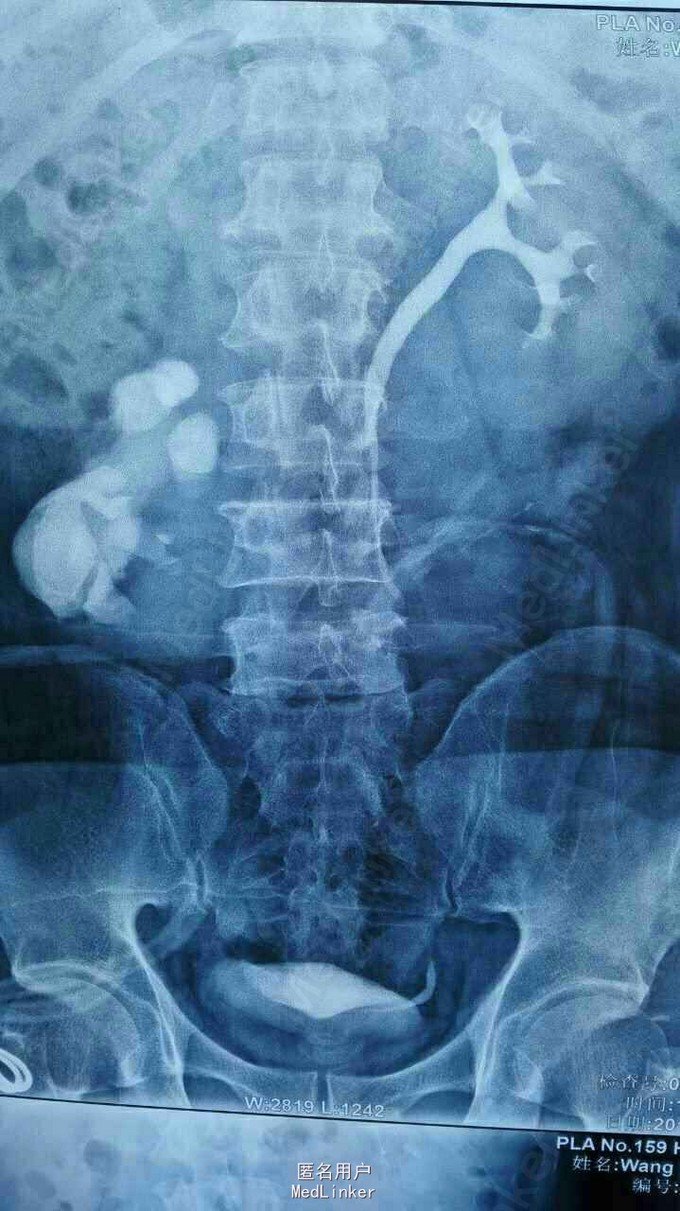

异位肾结石

因反复右侧腹部疼痛5年入院。 5年无诱因出现右侧腹部疼痛,呈阵发性胀痛,无发热,无恶心、呕吐,无尿频、尿急,无肉眼血尿,大便正常,体重无明化。

腹平软,全腹无明显压痛及反跳痛,肠鸣正常,肾区无隆起无叩痛。 辅查,肾功能、血生化均正常。

诊断:右侧异位肾结石并肾积水。 拟行经皮肾镜碎石取石术,但因庙小,患者要求上级医院治疗。

请问各位如遇到这样患者如何治疗,是切肾还是取石?